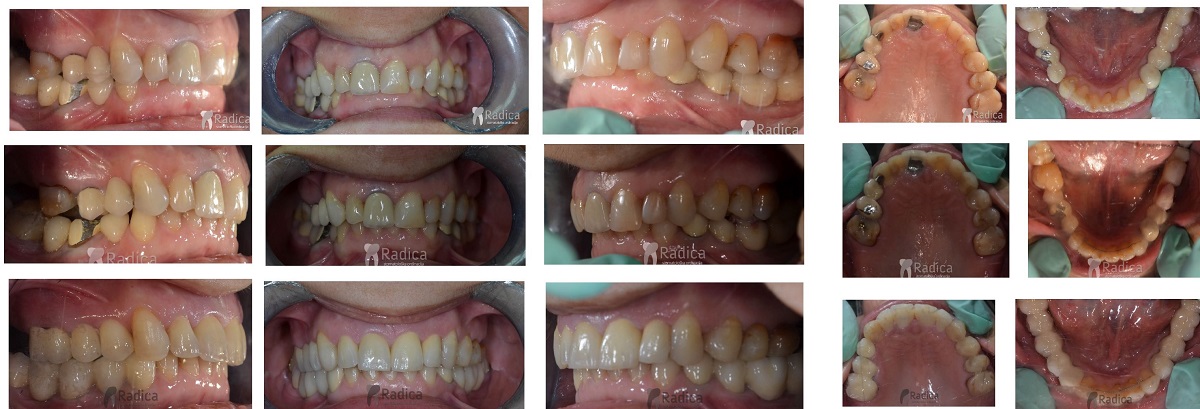

U galeriji slika su prikazani klinički slučajevi ovakvih odraslih pacijenta bilo da se radi samo o ortodontskoj terapiji ili predprotetskoj ortodonciji.

U sljedećem primjeru su se na mjesto donjih ekstrahiranih prvih molara stavili dentalni implantati prije ortodontske terapije (rad dr. Gorana Radice) i ujedino su služili za pojačenje sidrišta tijekom ortodontske terapije. Nakon ortodontske terapije estetski su se preoblikovali sjekutići i napravile nove krunice (također rad dr. Gorana Radice).